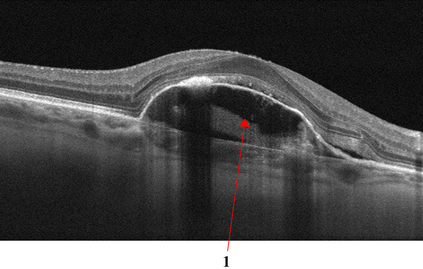

Optical coherence tomography (OCT) is a non-invasive imaging technique with extensive clinical applications in ophthalmology. OCT enables the visualization of the retinal layers, playing a vital role in the early detection and monitoring of retinal diseases. OCT uses the principle of light wave interference to create detailed images of the retinal microstructures, making it a valuable tool for diagnosing ocular conditions. This work presents an open-access OCT dataset (OCTDL) comprising over 1600 high-resolution OCT images labeled according to disease group and retinal pathology. The dataset consists of OCT records of patients with Age-related Macular Degeneration (AMD), Diabetic Macular Edema (DME), Epiretinal Membrane (ERM), Retinal Artery Occlusion (RAO), Retinal Vein Occlusion (RVO), and Vitreomacular Interface Disease (VID). The images were acquired with an Optovue Avanti RTVue XR using raster scanning protocols with dynamic scan length and image resolution. Each retinal b-scan was acquired by centering on the fovea and interpreted and cataloged by an experienced retinal specialist. In this work, we applied Deep Learning classification techniques to this new open-access dataset.